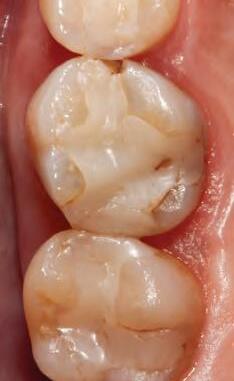

DISTO-OCCLUSAL CLINICAL CASE